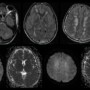

(a-c) FLAIR images show multiple small ill-defined confluent white matter hyperintensities involving bilateral frontal periventricular regions and bilateral centrum semiovale (internal watershed areas), bilateral cerebellar white matter. Roght middle cerebellar peduncle, posterior limb of internal capsule, thalami and splenium of corpus callosum. (d-g) Small punctate areas of diffusion restriction are seen in bilateral basal ganglia. Patchy diffusion restriction is seen in bilateral centrum semiovale.

(h-j) SWI images (magnitude) show multile microbleeds diffusely scattered in the involved regions (cerebellar white matter, middle cerebellar peduncles, periventricular white matter and centrum semiovale): WALNUT KERNEL PATTERN. These are more in the central white matter than at gray-white matter junction.